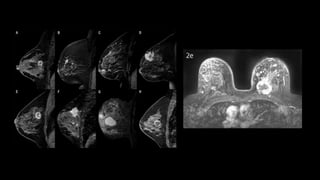

• RM mamaria

• Anormalidades de tejidos blandos locales

• Evaluación de lesiones ocultas, multifocales o bilaterales

• Respuesta a neoadyuvancia (previa y posterior)

• Cirugía conservadora en pacientes de alto riesgo.

• Reconstrucción mamaria previa (biopolímeros, implantes)